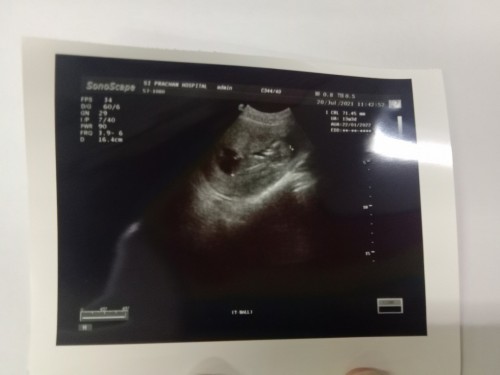

คุณแม่อายุ38ท้อง3ตอนนี้15สัปดาห์กังวลมากเลยจร้า